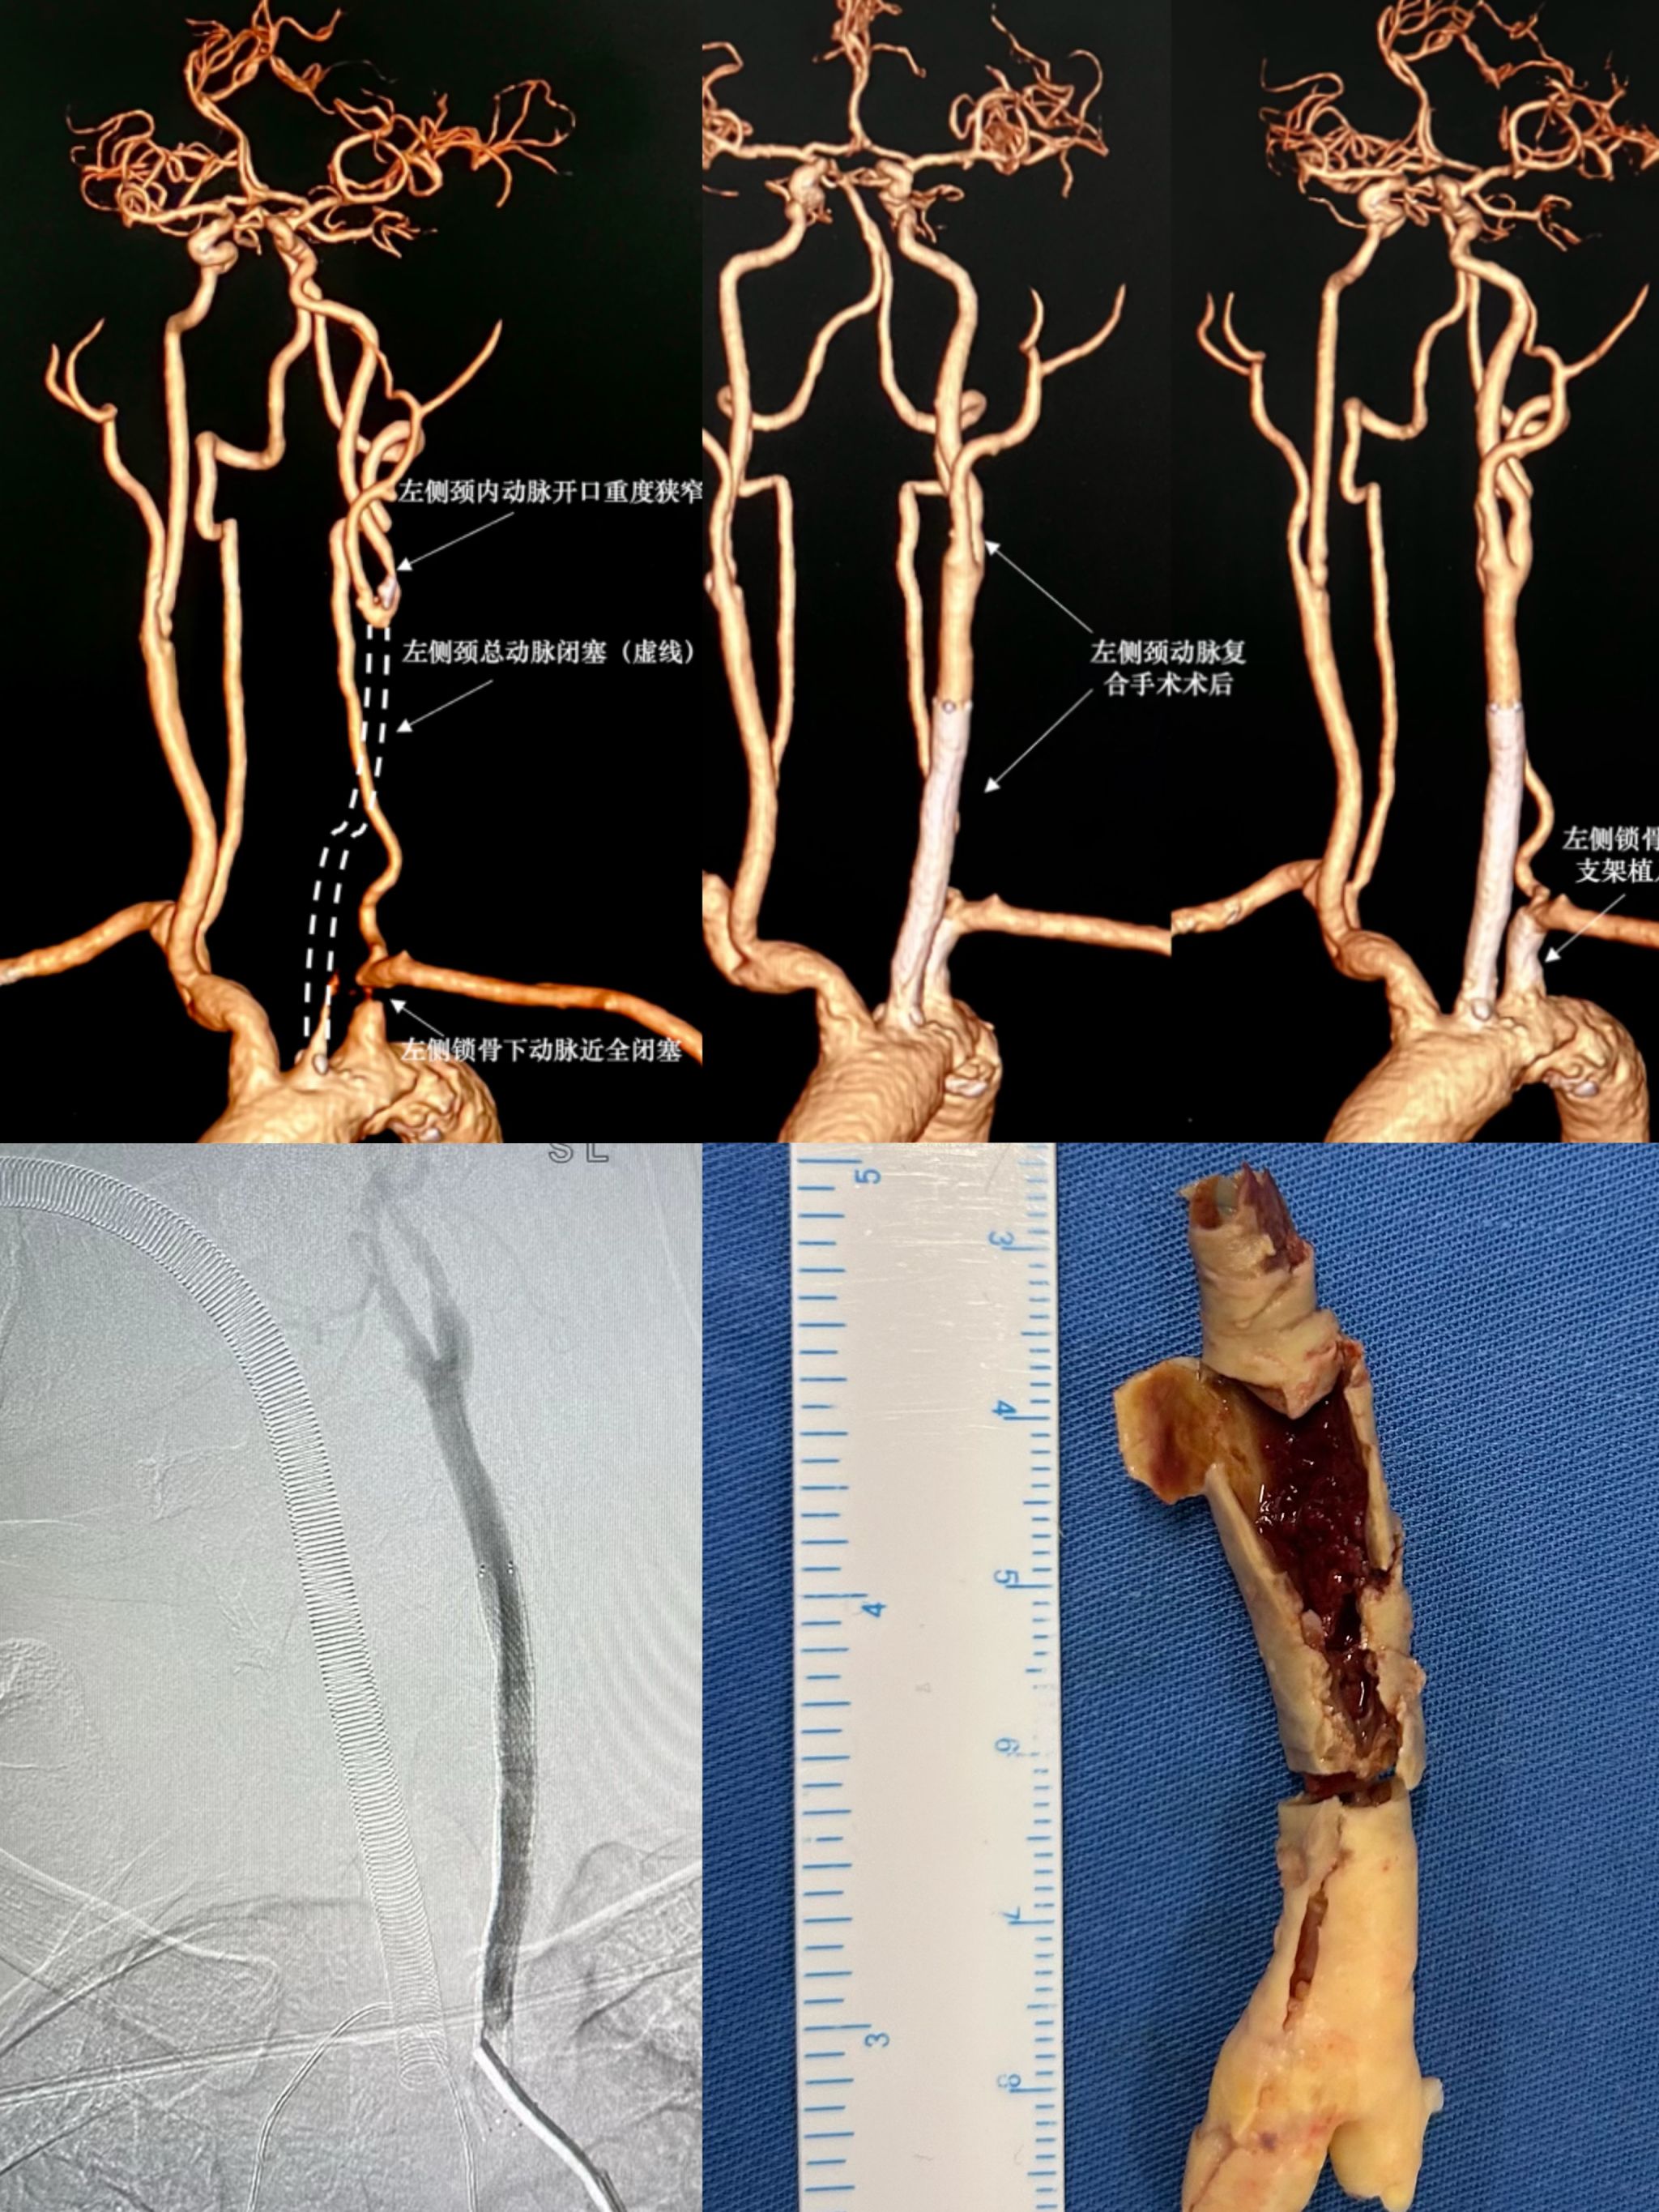

北医三院机场院区介入血管外科顺利完成首例颈动脉长段闭塞复合手术